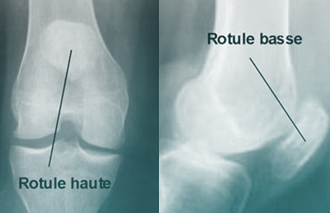

• Rotule trop haute (Patella Alta) : Si le tendon rotulien est trop long, la rotule se positionne trop haut par rapport à la trochlée. Elle n’est plus bien guidée au début de la flexion, ce qui crée une instabilité.